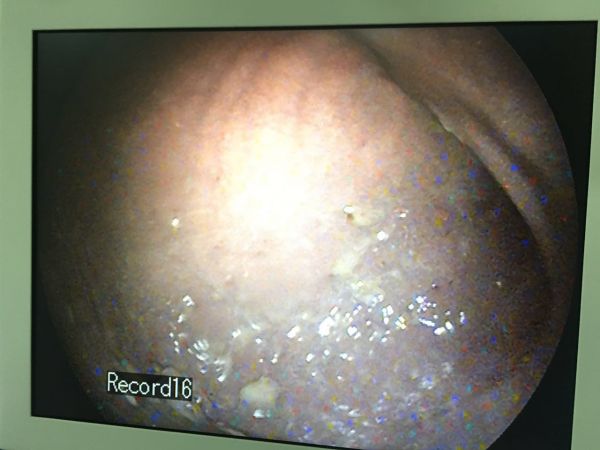

5、1.4kg,白贵宾,小白,1岁,食道异物,内窥镜取出3公分的骨头和大量棉花,食道大面积糜烂、出血。

6、盐城建湖宠物医院转诊,博美,球球,4.0kg,食道异物,内窥镜检查发现食道卡到骨头,食道出血,糜烂严重,内窥镜取出。

7、 淮安同行介绍转诊,一岁,比熊犬,食道异物,食道卡到骨头四天,内窥镜食道镜检查食道严重糜烂、溃疡、出血。内窥镜取出5公分的脊椎骨。